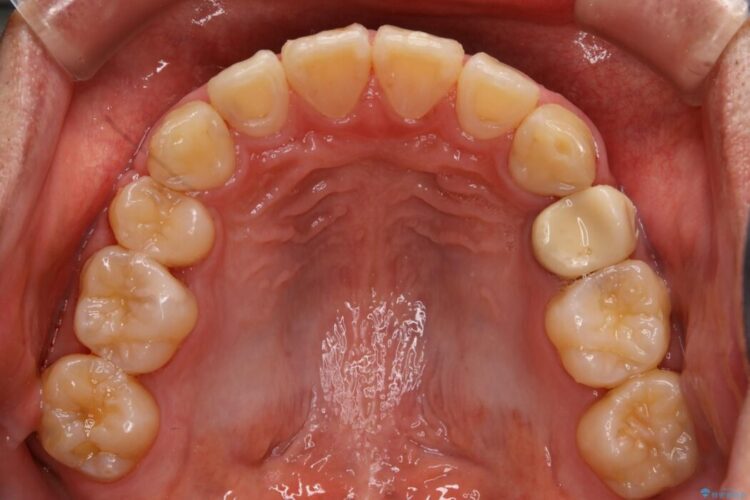

【30代男性】ワイヤー矯正で出っ歯とガタつきの改善

上の歯の出っ歯と下の歯のガタつきが気になるとご来院された患者様です。

出っ歯とガタつきの改善には抜歯が必要と診断し、上下左右第一小臼歯を抜歯することとしました。

治療後について

ワイヤー矯正、マウスピース矯正、それぞれの特性、得意な治療がありますので、患者様の状態に合わせた治療器具の選択が大事となります。